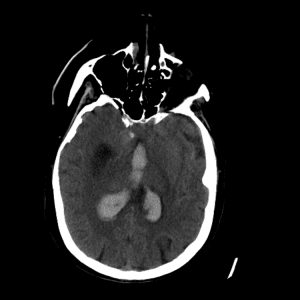

Non-traumatic Head CT Cases

Classic Cases

Includes classic examples of cases commonly seen on call.

Basilar artery thrombosis

Case #8